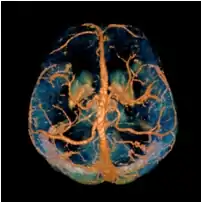

Quantitative susceptibility mapping (QSM) provides a novel contrast mechanism in magnetic resonance imaging (MRI) different from traditional susceptibility weighted imaging.[1][2][3][4][5] The voxel intensity in QSM is linearly proportional to the underlying tissue apparent magnetic susceptibility, which is useful for chemical identification and quantification of specific biomarkers including iron, calcium, gadolinium, and super paramagnetic iron oxide (SPIO) nano-particles. QSM utilizes phase images, solves the magnetic field to susceptibility source inverse problem, and generates a three-dimensional susceptibility distribution. Due to its quantitative nature and sensitivity to certain kinds of material, potential QSM applications include standardized quantitative stratification of cerebral microbleeds and neurodegenerative disease, accurate gadolinium quantification in contrast enhanced MRI, and direct monitoring of targeted theranostic drug biodistribution in nanomedicine.

In principle, any 3D gradient echo sequence can be used for data acquisition. In practice, high resolution imaging with a moderately long echo time is preferred to obtain sufficient susceptibility effects, although the optimal imaging parameters depend on the specific applications and the field strength. A multi-echo acquisition is beneficial for accurate B0 field measurement without the contribution from B1 inhomogeneity. Flow compensation may further improve the accuracy of susceptibility measurement in venous blood, but there are certain technical difficulties to devise a fully flow compensated multi-echo sequence.

COSMOS assumes a model-free susceptibility distribution and keeps full fidelity to the measured data. This method has been validated extensively in in vitro, ex vivo and phantom experiments. Quantitative susceptibility maps obtained from in vivo human brain imaging also showed high degree of agreement with previous knowledge about brain anatomy. Three orientations are generally required for COSMOS, limiting the practicality for clinical applications. However, it may serve as a reference standard when available for calibrating other techniques.